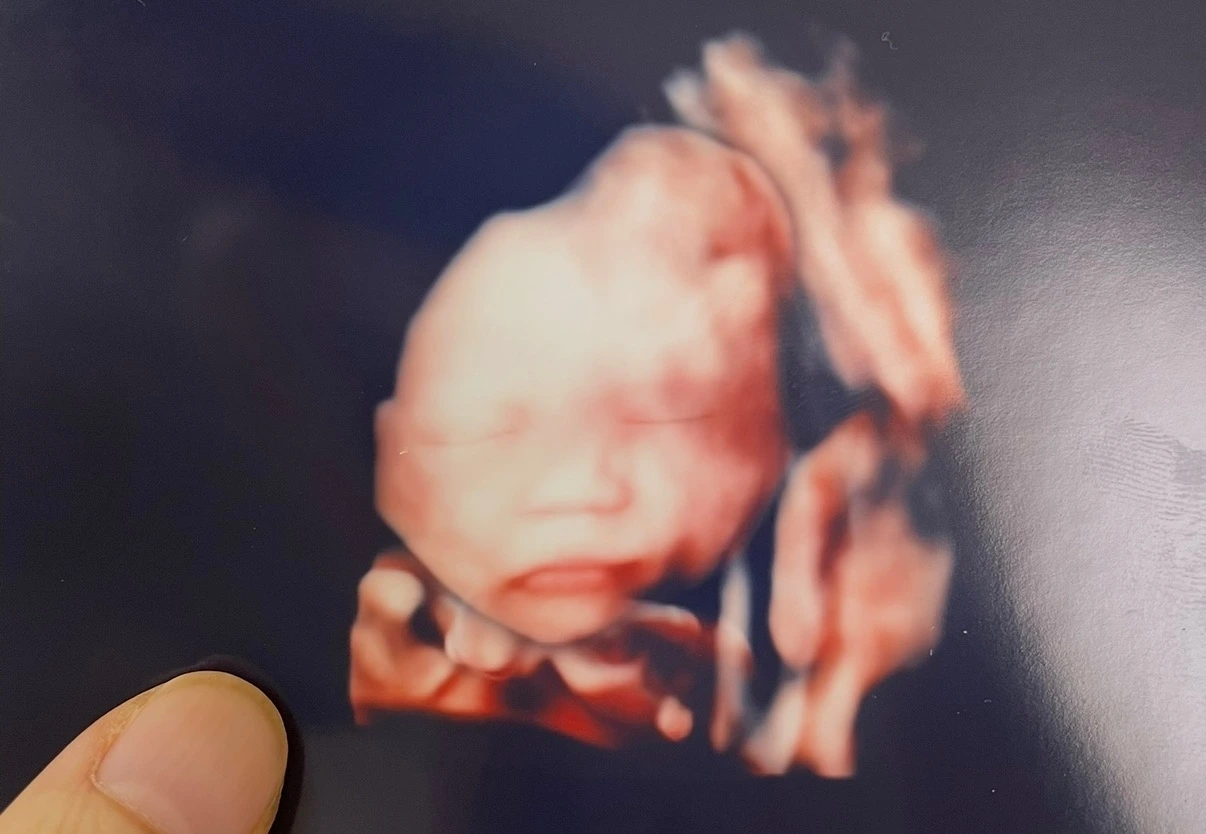

뭘 했는지도 모르는 2주가 지나고 정밀초음파 날이 됐다. 남편이 밀어주는 휠체어를 타고 산부인과 층으로 내려갔다. 보통 30분 정도 걸린다고 했다. 그런데 교수님은 아가의 머리끝부터 발끝까지 어디 하나 빠뜨리는 구석이 있을까 1시간 가까이 봐주셨다. 그리고 사진을 뽑아 주셨다.

“아가가 아빠를 많이 닮은 거 같네요.”

조용히 건네주시는 말투에는 걱정과 배려가 듬뿍 담겨 있었다. 잘 버텨보자고, 할 수 있다고. 아가 사진을 보며 힘내라고, 누워 있는 내 다리를 톡톡 두드려 주셨다. 사진을 꽉 쥐고 밖으로 나오니, 나보다 키가 한참 큰 담당 간호사 선생님이 고개를 숙여 귓속말을 건네셨다.

“오늘 교수님이 일부러 오래 봐주셨어요. 힘내라고, 걱정하지 말라고. 사진도 원래 안 뽑아주시는데 그냥 해주신 거 같아요. “

사진을 보니 너무 예뻤다. 가만히 눈을 감고 있는 아가를 보니 뭐라 형용할 수 없는 감정이 벅차올랐다.

내 아가.

우리 아가.